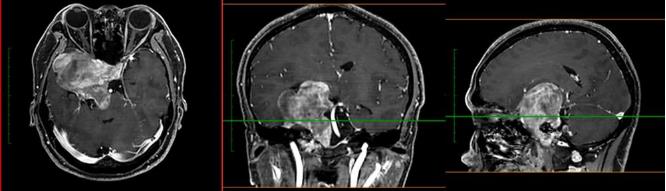

神經(jīng)外科濮春華主任醫(yī)師和團(tuán)隊(duì)在顯微鏡下嫻熟地操作,11個(gè)小時(shí)后, “盤踞”在中顱窩處的腫瘤被近全切除,一個(gè)月后,殘余在后顱窩的腫瘤也順利被“摘除”,兩次手術(shù)總計(jì)20余小時(shí),最終獲得成功。術(shù)后病理證實(shí)軟骨及黏液基質(zhì)的腫瘤,符合軟骨肉瘤 II級(jí)。

病理結(jié)果回報(bào)后,神經(jīng)外科第一時(shí)間邀請(qǐng)放療科高云生主任協(xié)助會(huì)診,根據(jù)術(shù)后復(fù)查MR的結(jié)果,為減少?gòu)?fù)發(fā)可能,決定為小成進(jìn)行質(zhì)子治療。如今,小成恢復(fù)良好,頭暈和視力下降等癥狀得到明顯的改善,已經(jīng)順利從神經(jīng)外科出院。